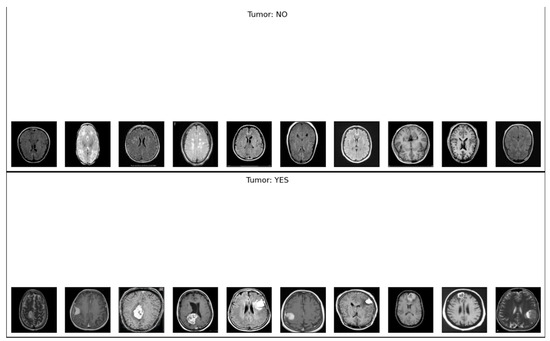

3.2. Dataset Description

The BR35H dataset from Kaggle [36] consists of 3000 pre-labeled MRI brain scans, equally divided into 1500 tumor images and 1500 normal samples. This dataset has been widely utilized for supervised learning and classification tasks. A detailed overview of the dataset, including representative samples of benign and malignant MRI images, is presented in Table 1. However, a key limitation of the BR35H dataset is that it provides images only at the slice level, without metadata regarding the number of unique patients. Consequently, each MRI slice was treated as an independent data point during model development.

Figure 2. Sample images with brain tumor (Including T1 and T2 weight images).

Ai 06 00305 g002